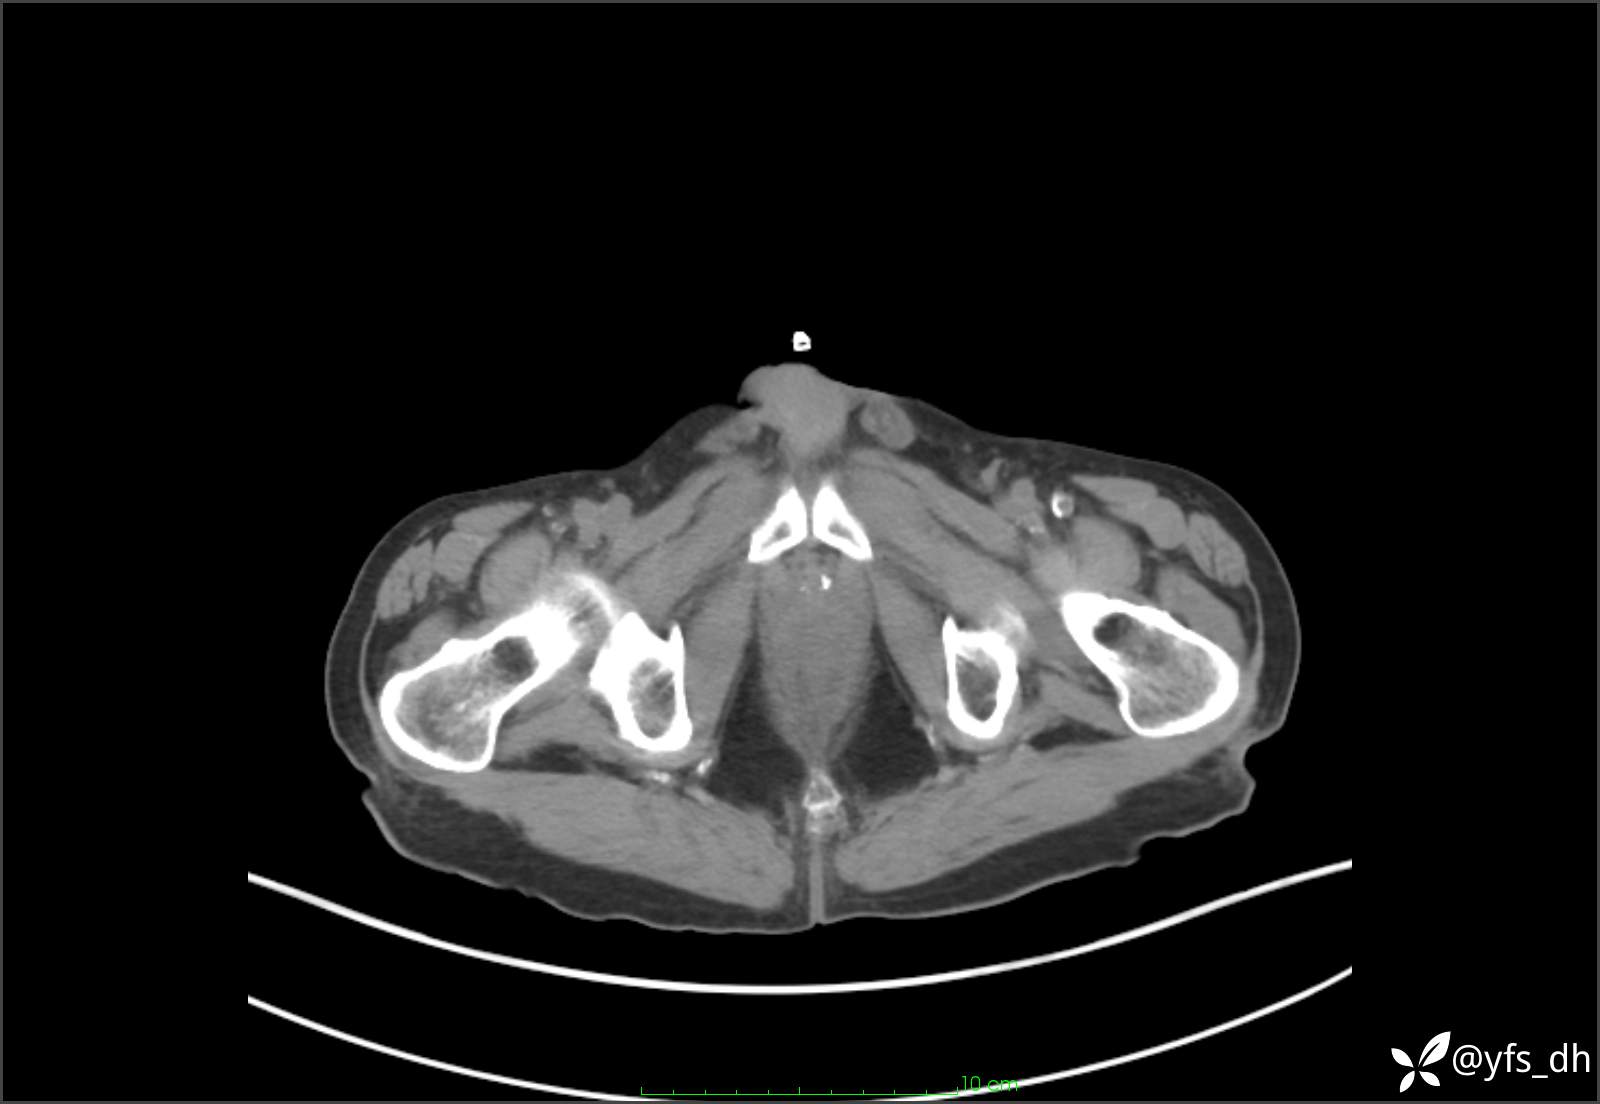

1.简要病史:患者4天前突发上腹部疼痛不适,但可以忍受。3小时前饭后突然加重,不能忍受后就诊。

2.简要手术记录:术中见腹盆腔大量肠液及粪便,乙状结肠中下段见一约3cm的破口。